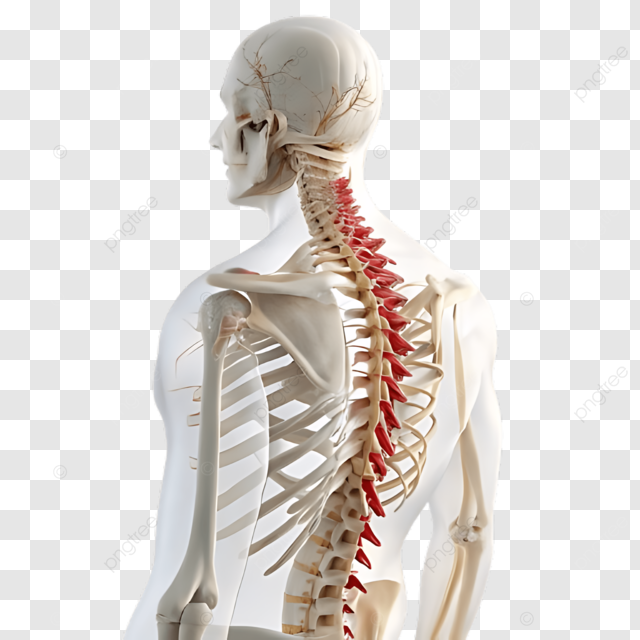

Cirugía de Columna

La cirugía de columna es una rama altamente especializada enfocada en el tratamiento de patologías que afectan la estabilidad, movilidad y funcionalidad de la columna vertebral, incluyendo hernias discales, estenosis espinal y enfermedades degenerativas.